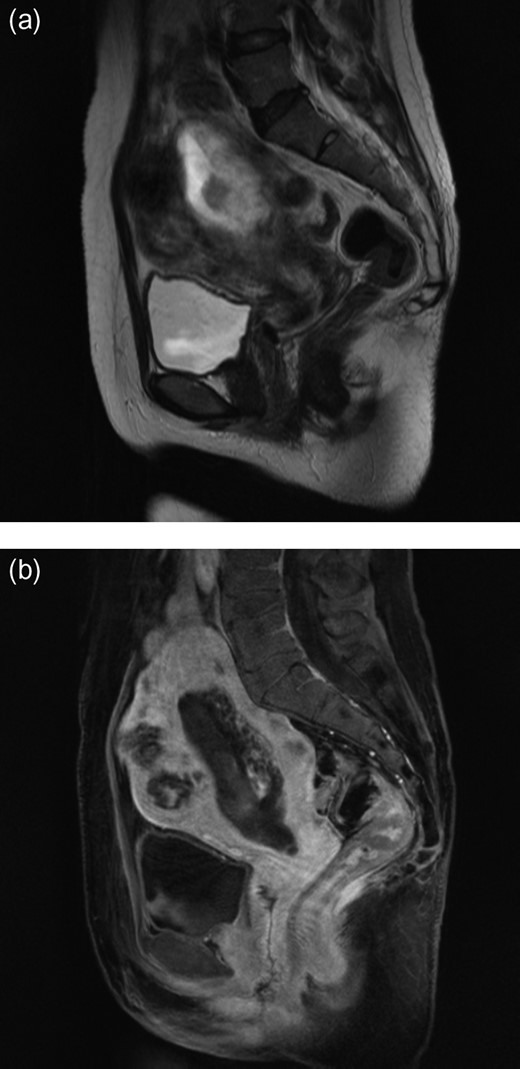

A 50-year-old woman, Gravida 3, Para 1, presented to our department with irregular genital bleeding for 2 months. Her last menstrual period had been 2 months before. Her obstetrical history included a normal vaginal delivery 13 years before and two spontaneous abortions 8 and 11 years previously. Transvaginal ultrasonography showed an enlarged uterus with endometrial thickening with an echogenic pattern (Fig. 1). As endometrial cancer was suspected first, an endometrial biopsy and magnetic resonance imaging (MRI) were performed. The endometrial biopsy revealed decidual tissues, and the MRI revealed invasion of a uterine corpus tumor into the myometrium (Fig. 2). A week later, the patient admitted to the hospital with continuation of irregular vaginal bleeding. Second endometrial biopsy was done and serum β-human chorionic gonadotropin (hCG) level was also measured owing to suspicion of a hydatidiform mole. The serum hCG level was over 225 000 mIU/mL, and the endometrial biopsy revealed a complete hydatidiform mole. Because the patient's hemoglobin level was 7.0 g/dL, owing to the continuation of uterine bleeding, we transfused 800 mL of red cell concentrate and discharged the patient. A lung metastasis, 1 cm in diameter, was observed on a contrast computer tomography scan (Fig. 3), and an invasive mole with lung metastasis was diagnosed. Because the patient did not desire preservation of her uterus or adnexa, we offered her a total abdominal hysterectomy (TAH) and bilateral salpingo-oophorectomy (BSO). At her next consultation for the continuous genital bleeding, a tumor of the right labium minus was recognized and histologically confirmed as a metastatic lesion of the mole (Fig. 4). The patient underwent TAH and BSO. Unfortunately, a tumor of right labium minus had spontaneously fallen off during surgery. In a gross specimen, molar vesicles were recognized at the uterine corpus with the right ovary a little swollen (Fig. 5). The invasions into myometrium by both villi and the trophoblasts were histopathologically confirmed (Fig. 6). In addition to the labium minus tumor, a metastatic lesion of the right ovary was diagnosed. The final pathological diagnosis was metastatic invasive hydatidiform mole, Stage III. The patient's serum hCG level fell to 10 779 mIU/mL after her operation. The patient was then started on administered methotrexate 20 mg/body intramuscularly, 5 days a week at 2 weeks intervals. Serum hCG levels are measured for the estimation of chemotherapy [4]. Her serum hCG level rapidly fell to 1.2 mIU/mL after four courses of methotrexate (Fig. 7). Two additional courses of methotrexate were completed, and there has been no evidence of recurrent disease for 6 months.

MRI showing invasion into the uterine cervix (a) and myometrium invasion in the posterior wall of the uterus (b).